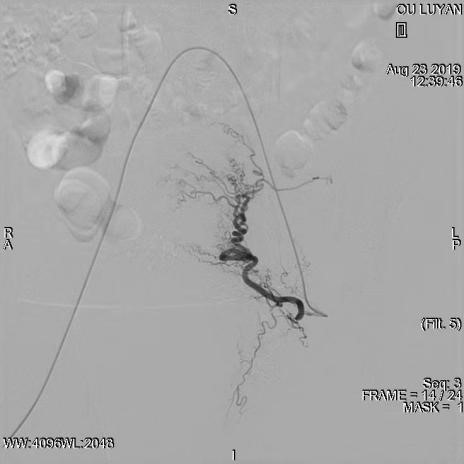

综合评估后考虑患者为Ⅱ型子宫切口妊娠,与患者及家属沟通后决定选择药物杀胚同时行双侧子宫动脉栓塞术。DSA显示双侧子宫动脉增粗、迂曲,均注入150-560um明胶海绵颗粒,造影显示栓塞满意。血β一HCG下降后在宫腔镜、B超引导下清除妊娠病灶,积极终妊。8月27日,手术过程进行顺利,未输血,患者于9月1日出院,后期继续加强康复治疗,预防远期并发症宫腔粘连发生。

右侧子宫动脉稍增粗、迂曲

栓塞术后右侧子宫动脉未见显影